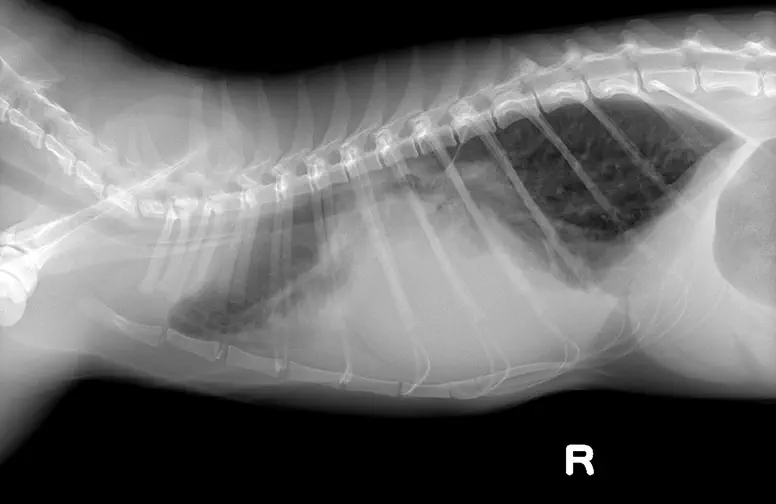

レントゲン検査

心臓の大きさや形状、血管の太さなどを評価します。また、気管や気管支、肺野全体の評価ができます。

正常な猫の胸部

先天性心疾患(PDA)の猫の胸部